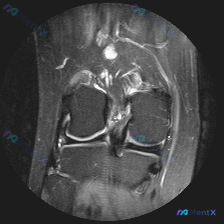

膝关节MRI见髌股关节软骨异常+积液,这个病例鉴别诊断容易漏什么?

看到这张膝关节MRI轴位图像,整理了完整的分析思路分享给大家。 病例影像基本信息 这是膝关节MRI轴位T2加权(或质子密度加权)图像,层面位于股骨远端靠近髌股关节水平,可清晰显示前方髌骨、中部股骨滑车、后方腘窝血管肌肉结构。 核心影像发现 1. 髌股关节软骨异常:髌骨后方关节软骨可见线状/层状高信号...